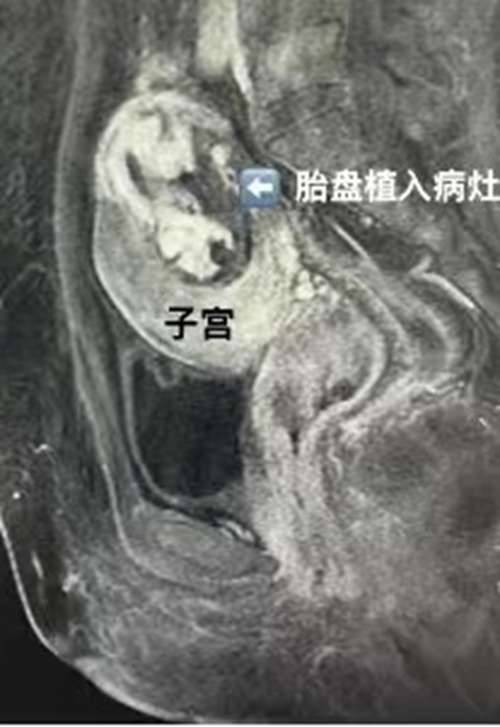

33歲的張女士(化名)去年查出懷孕,然而6個月產檢時卻發(fā)現(xiàn)胎兒異常,在當?shù)蒯t(yī)院做了引產術,引產過程中胎盤并未自然娩出,手取胎盤也失敗。引產后磁共振提示“胎盤植入”,而且?guī)缀醮┩缸訉m肌層。

#術前盆腔增強磁共振 >>

#術后盆腔增強磁共振 >>